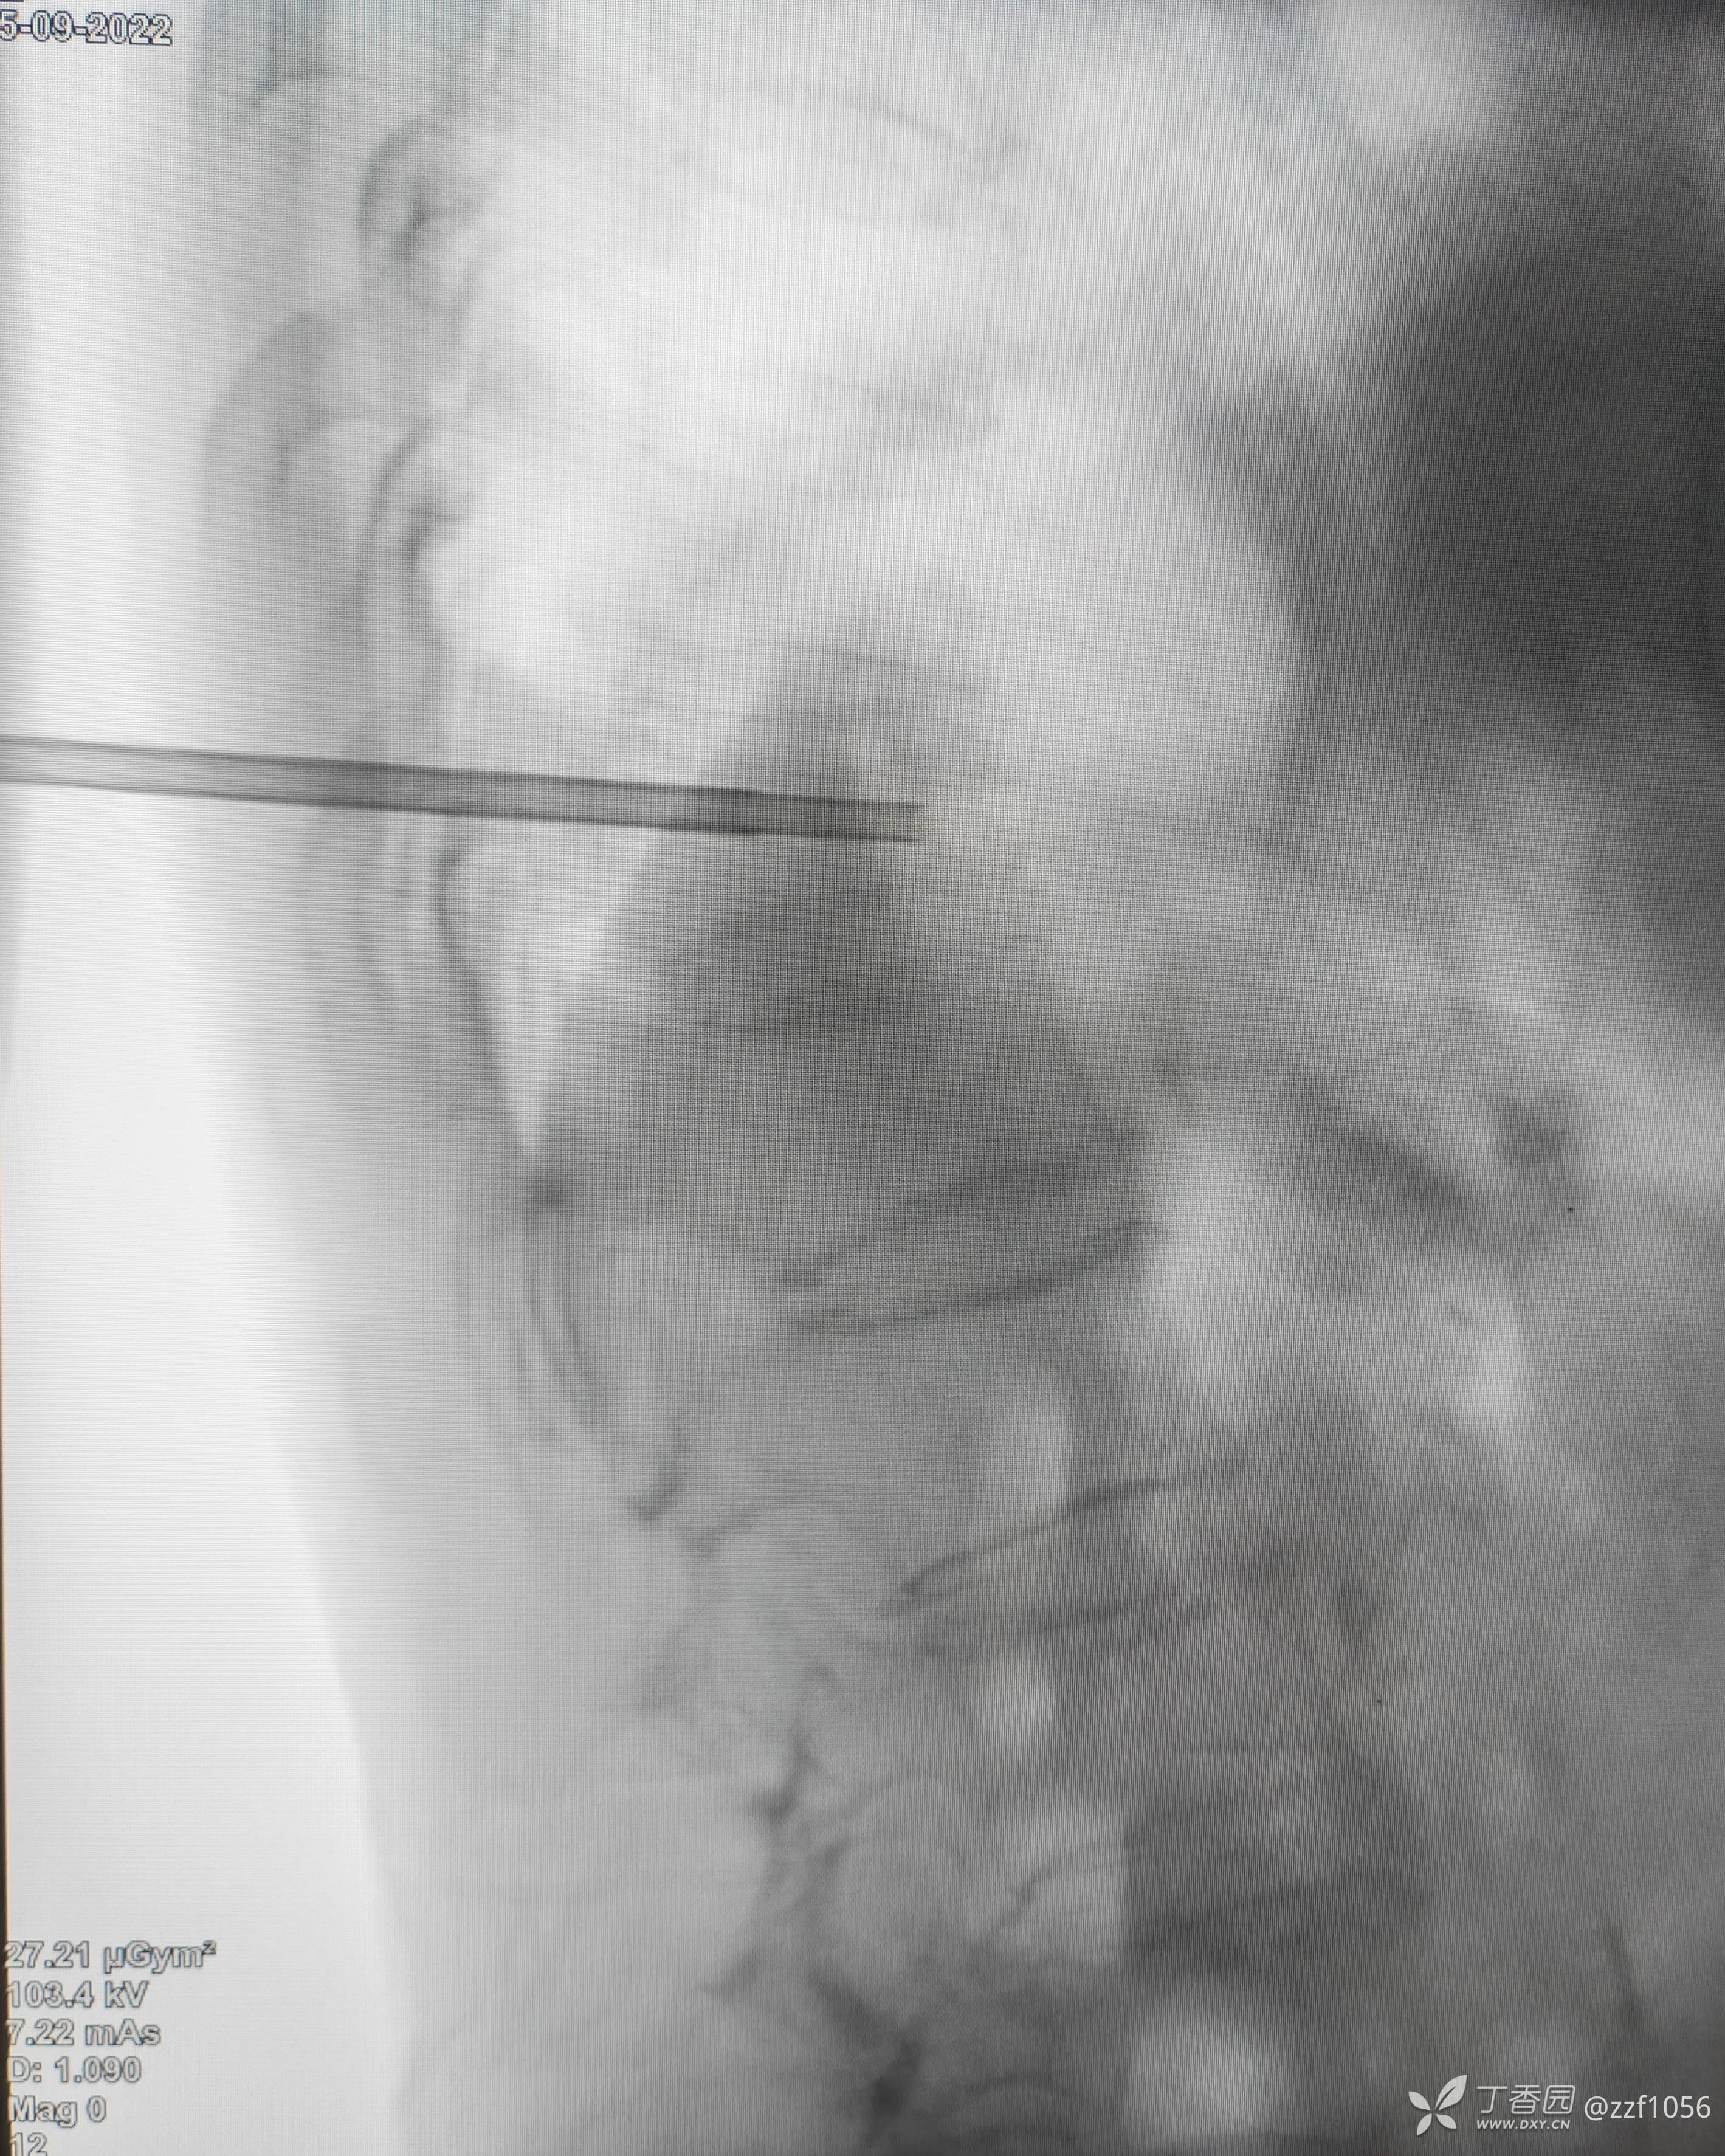

病例二(非我病例,单侧穿刺)

患者老年男性,85岁

第一次甲医院术后

战友们觉得如何?骨髓泥量约3、4ml,那么单侧穿刺能否说的过去?